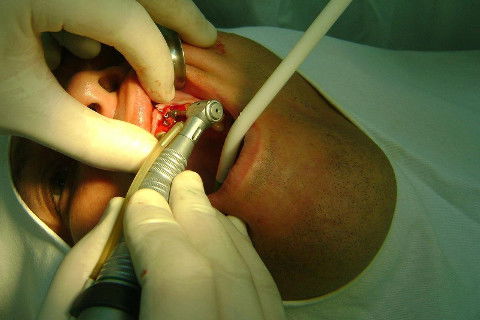

Cirurgia realizada hoje de manhã...No planejamento percebi medindo espessura do rebordo com especímetro que as medidas não estavam muito boas, ou o ideal, em torno de 4,5 a 5 mm ate´o terço médio do rebordo e melhorava no final, com 6 a 7 mm. Optei então por uma pequena expansão usando os expansores rosqueáveis. Aconteceu uma pequena fenestração na hora da fixação dos implantes, especialmente na região do 22 que fraturou o início da tábua óssea, mas não me preocupei porque não foi mais do que 2 mm de fratura em direção apical, o implante ficou infraósseo e com boa estabilidade (60 N no 21 e 40 N no 22). Esta fratura tb não deixou osso completamente solto, foi do tipo galho verde, deixei em posição e suturei normalmente. Só não fiz e nem estava planejado carga imediata mesmo, mais pelo motivo da oclusão inadequada do caso.